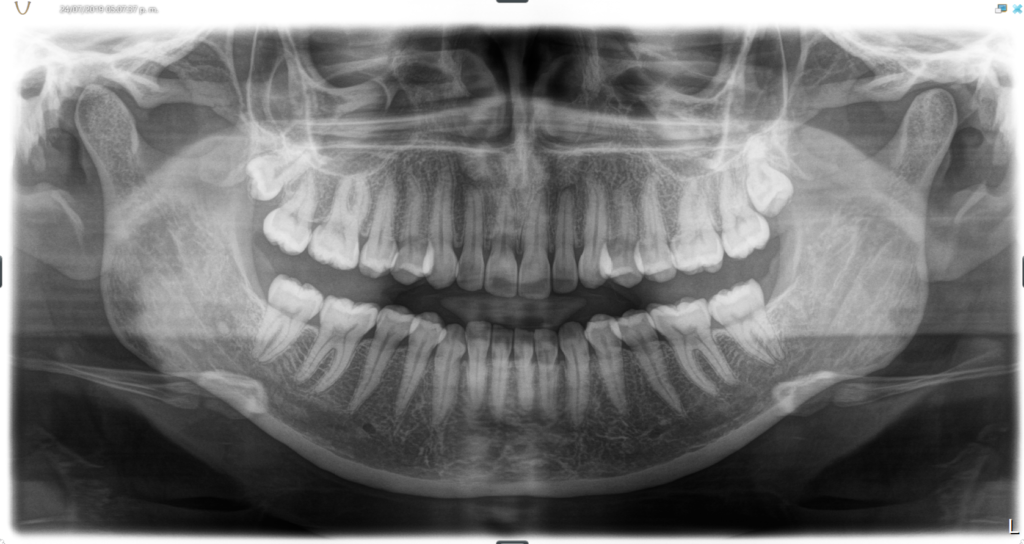

After you have finished with the check in one of our dental assistance will escort you to start taking x-rays. X-rays help the dentist to see things that are not visible in the oral examination and to assess the condition of teeth below the gum line, such as the jaw bone and nerves.